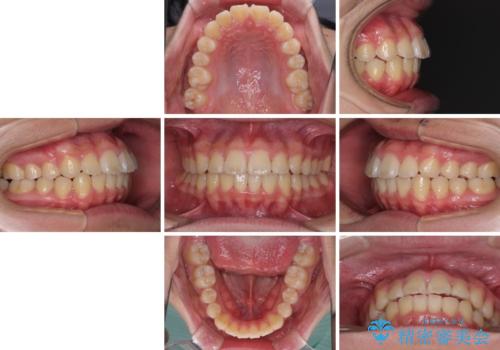

前歯のデコボコを短期間で治療 目立たないワイヤー矯正

- 上下前歯のデコボコを改善したいとのことで来院された患者様です。

自己管理を減らしたいとのことで、ワイヤー装置による矯正治療を行うこととしました。

中学生と言うこともあり、1年強の短期間で終了しました。

歯磨きがしっかりとできないと虫歯になるリスクがありましたが、治療期間中は清潔な状態を保っていただけました。